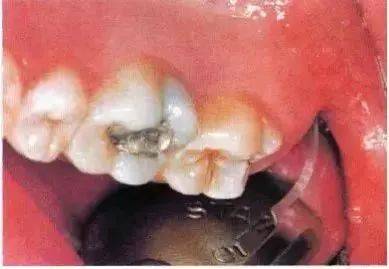

去除颊侧部分骨阻力后,用装在反角机头上的纺锤形车针切割牙冠。用柔韧的小拉钩保护舌侧的黏骨膜(及舌神经)。